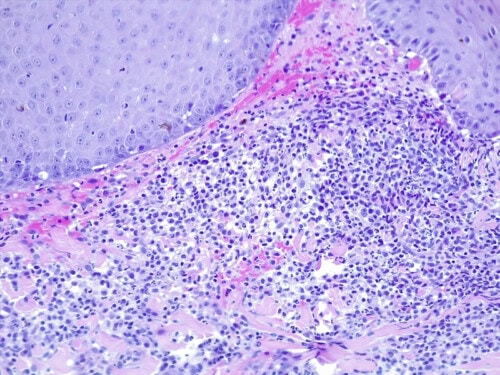

Un examen histopathologique est demandé au LAPVSO (Dr Frédérique DEGORCE). Les biopsies mettent en évidence des lésions surélevées focales en plaques, caractérisées par une une hyperplasie psoriasiforme, épidermique, avec spongiose, œdème des acanthocytes et une forte exocytose de granulocytes neutrophiles, évoluant en pustules granulocytaires sous et intra-cornées qui s’impétiginisent. Dans le derme sous-jacent un infiltrat forme une plage cellulaire d’allure lichénoïde, les cellules se collectant sous la membrane basale épidermique et entourant les apex folliculaires. L’infiltrat cellulaire est formé de granulocytes neutrophiles, de cellules histiocytoïdes et petits lymphocytes et de plasmocytes. Une vésiculation hydropique est présente à l’interface des structures épithéliales ainsi que quelques corps apoptotiques dans leur couche basale. Aucun élément figuré, ni parasitaire, ni fongique n’a été détecté sur les différents plans de section effectués, ni sur la réaction au PAS. (photos 5 à 8)

Photos 6 et 7 : HES*200 plage cellulaire d’allure lichénoïde et pustule granulocytaire sous et intra-cornée, vésiculation hydropique à l’interface des structures épithéliales et corps apoptotiques dans la couche basale